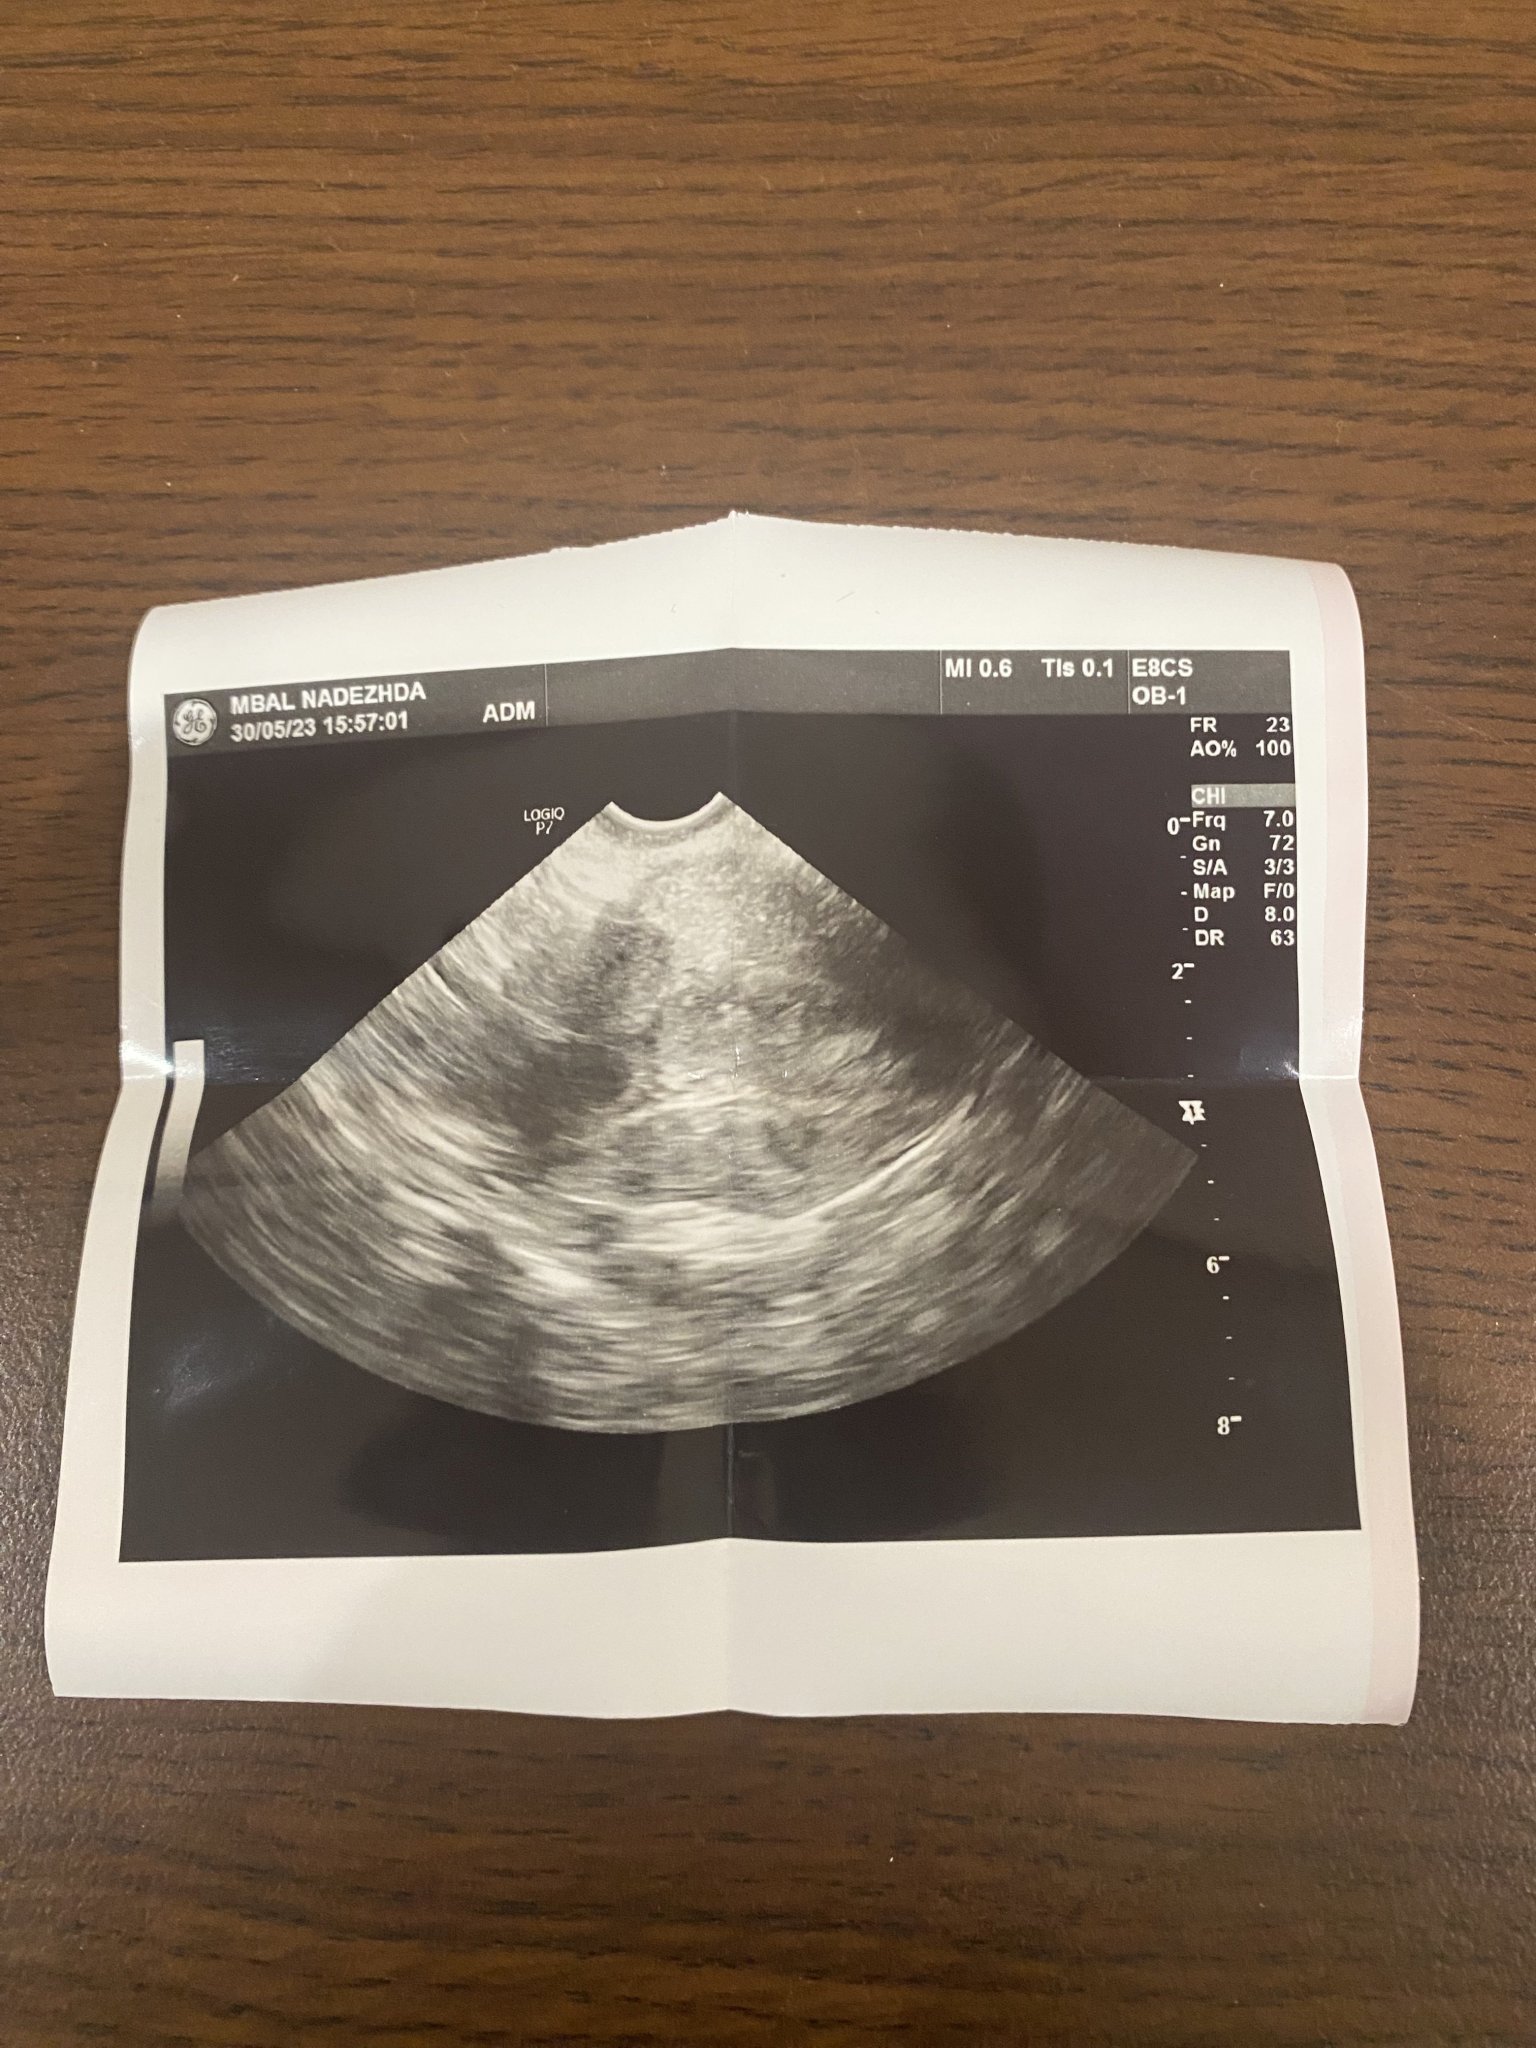

Как се вижда яйчникът и жълтото тяло?